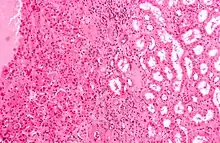

The main differential diagnosis of renal oncocytoma is chromophobe renal cell carcinoma oncocytic variant, which like the renal oncocytoma has eosinophilic cytoplasm, but has perinuclear clearing and, typically, some degree of nuclear atypia.

Micrograph of a renal oncocytoma. H&E stain. Micrograph of chromophobe RCC oncocytic variant, the main differential diagnosis of renal oncocytoma.

Micrograph of chromophobe RCC oncocytic variant, the main differential diagnosis of renal oncocytoma.